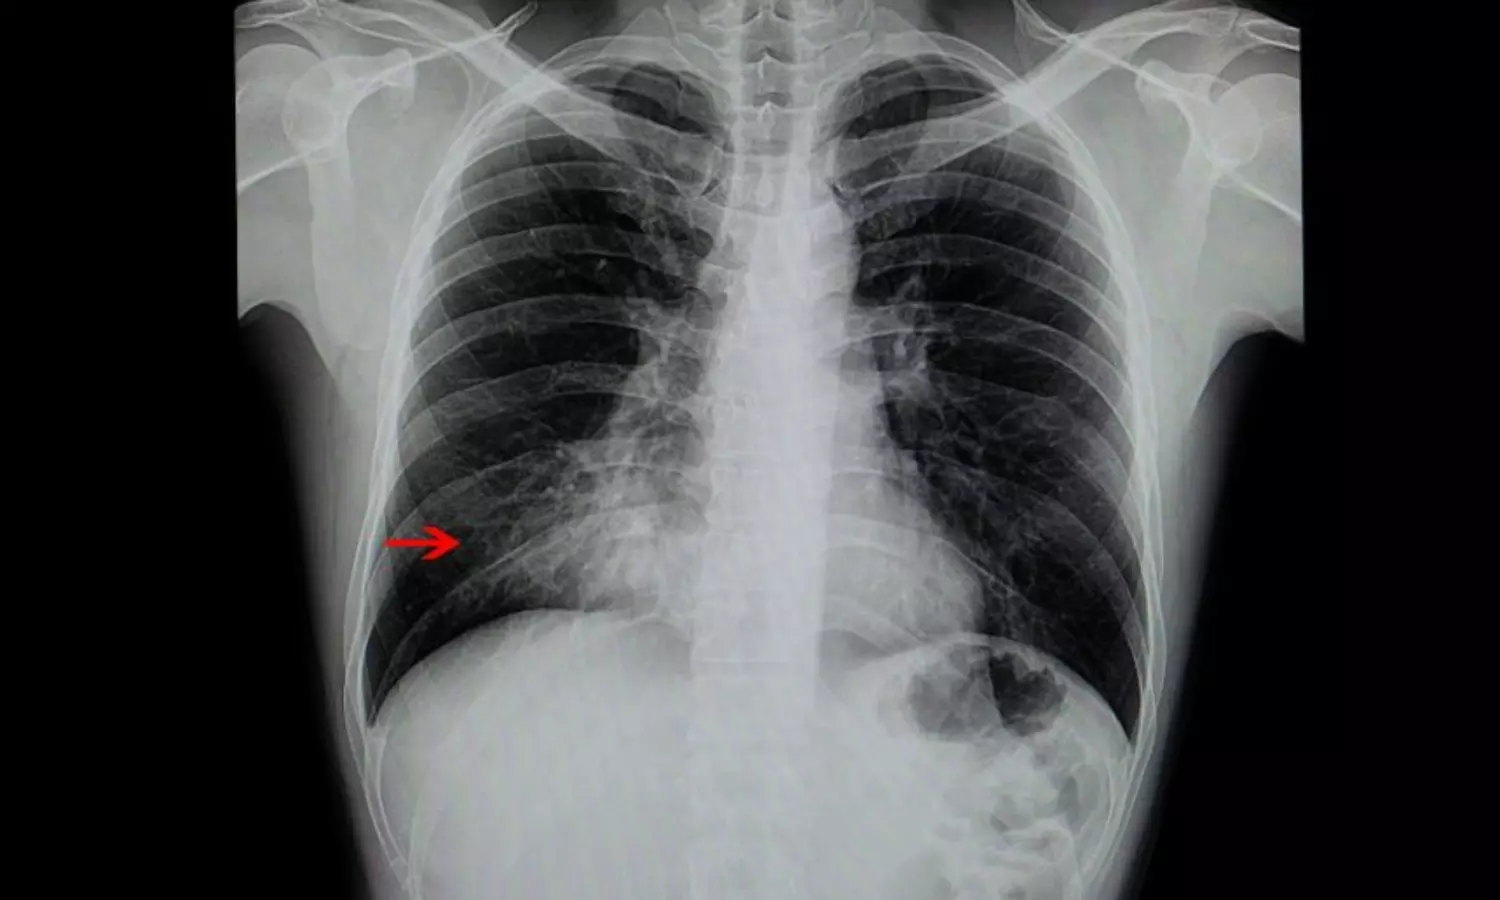

ഇന്ത്യയില്‍ അഞ്ചുവയസ്സില്‍ താഴെയുള്ള കുഞ്ഞുങ്ങളുടെ മരണത്തിനു ഏറ്റവും മുന്നിലായി നില്‍ക്കുന്ന കാരണം ന്യൂമോണിയാണ്. സാധാരണ ചുമയും ജലദോഷവുമെല്ലാമായി തുടങ്ങുന്ന ന്യുമോണിയയെ സൂക്ഷിക്കണമെന്നതിന്റെ തെളിവാണ് ഈ കണക്കുകകള്‍.

യുനിസെഫ് കണക്കുകള്‍ പ്രകാരം ഒരു ദിവസം 2,500 കുഞ്ഞുങ്ങള്‍ ന്യൂമോണിയ മൂലം മരിക്കുന്നു. ലോകത്താകെയുള്ള ന്യൂമോണിയ മരണങ്ങളില്‍ 20% ഇന്ത്യയിലാണ്. രോഗപ്രതിരോധ ശക്തികുറഞ്ഞ കുട്ടികളിലാണ് ന്യൂമോണിയ കൂടുതല്‍ അപകടകാരിയായി മാറുന്നത്.

ശ്വാസമെടുക്കാനുള്ള ബുദ്ധിമുട്ടാണ് കുട്ടികളില്‍ കാണുന്ന ന്യൂമോണിയായുടെ പ്രധാന ലക്ഷണം. തുടര്‍ച്ചയായ ചുമയും ഇടവിട്ടുള്ള പനിയും ന്യൂമോണിയായുടെ മറ്റൊരു ലക്ഷണമാണ്. നിര്‍ജ്ജലീകരണമാണ് മറ്റൊരു പ്രധാന ലക്ഷം കുട്ടികളുടെ ശരീരത്തില്‍ ജലാംശം പൂര്‍ണ്ണമായി ഇല്ലാതെയാക്കാന്‍ ന്യൂമോണിയ കാരണമാകുന്നു. രോഗവസ്ഥയിലുള്ള കുട്ടി ചുമയ്ക്കുമ്പോള്‍ ഛര്‍ദ്ദിക്കുന്നതും ന്യമോണിയായുടെ പ്രധാന ലക്ഷണമാണ്.